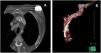

Con vistas a la planificación del procedimiento de extracción se realizó una tomografía axial computarizada (TAC) con reconstrucción 3D del trayecto de los electrodos. En las imágenes de la TAC se observa que el trayecto de los electrodos implantados más recientemente está centrado en el interior de la vena innominada y cava superior. Sin embargo, el recorrido de los electrodos más antiguos es diferente, estando apoyados completamente en la cara posterior y lateral de la innominada y cava, dando la impresión de estar situados en el espesor de la grasa perivascular y sin poder descartar su curso extravascular (fig. 2).

Ingresa en septiembre del 2021 por infección del dispositivo, con supuración, signos de infección local y cultivo de la herida positivo para Staphyloccocus aureus, sin presencia de infección sistémica. Hemocultivos negativos. En la región del bolsillo del generador del DAI-TRC, presenta una lesión granulomatosa de 0,5cm en tercio medio con exudado hemático. En la radiografía de tórax (fig. 1A y 1B) se visualizan los electrodos posicionados correctamente en las cavidades correspondientes. En el ecocardiograma transtorácico se observa uno de los electrodos ventriculares totalmente adherido al velo septal de la válvula tricúspide y el otro electrodo ventricular derecho que interfiere con el movimiento del velo anterior. Además, se detecta un defecto de coaptación central importante que condiciona una insuficiencia tricúspide severa.